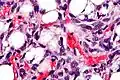

Lipoblasts are seen in liposarcoma[7] and characteristically have abundant multivacuolated clear cytoplasm and a dark staining (hyperchromatic), indented nucleus.